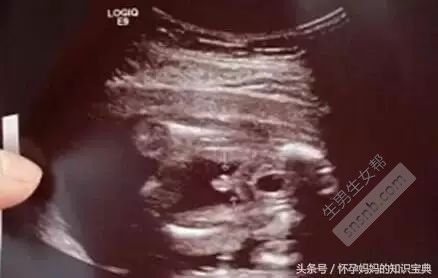

三、国外新奇小肿块原理

个别有经验的妈妈还有另一种看图方式:十一至十三周,所有的胎儿都会在双腿之间长出一个小肿块,而这个肿块的角度则会显示出它是个男孩还是女孩。据说如果小肿块翘起来30度以上就是男孩,但如果小角度就是女孩。请看下面的例子。

小肿块以一个陡峭的角度向上指,显示这个胎儿是个男孩。

如果你可以得到一张侧面图,那么它应该会给你提供一个很好的观察小肿块的角度。